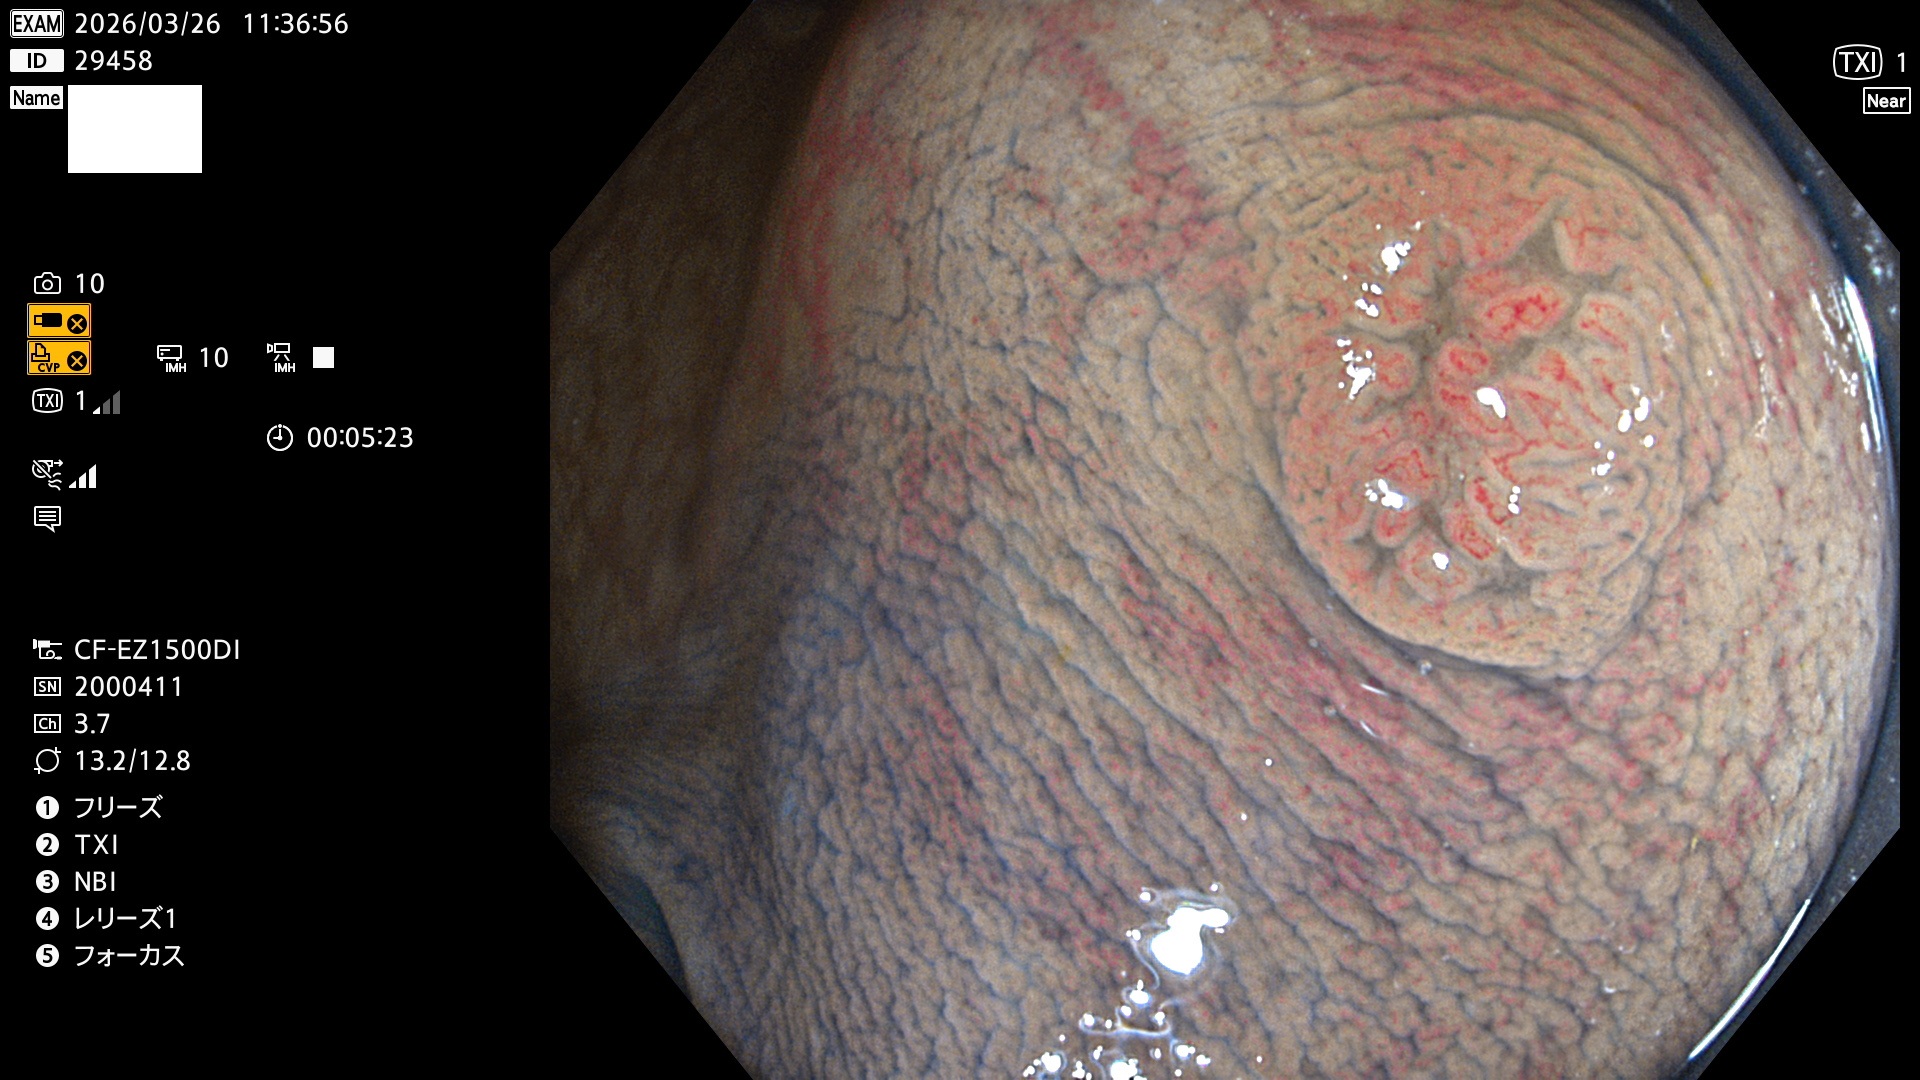

完全に平坦な物をUb、陥凹している物をUcと呼びます。Ubは認識が困難で、Ucはびらん(炎症)と紛らわしいために見落とされやすく、「内視鏡後・大腸癌」の原因になります。

毎週の検査(木・金・土・日)に発見されたUbとUc型・腺腫を、その週の日曜の夜にUPし1週間、提示します。

2026年3月26日〜3月29日の4日間(40件)4個 (Uc_ADR=4個/40人=10%)